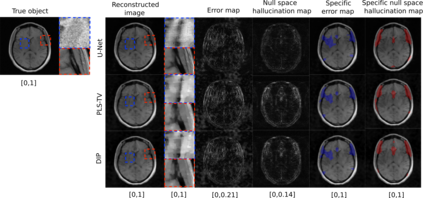

Tomographic image reconstruction is generally an ill-posed linear inverse problem. Such ill-posed inverse problems are typically regularized using prior knowledge of the sought-after object property. Recently, deep neural networks have been actively investigated for regularizing image reconstruction problems by learning a prior for the object properties from training images. However, an analysis of the prior information learned by these deep networks and their ability to generalize to data that may lie outside the training distribution is still being explored. An inaccurate prior might lead to false structures being hallucinated in the reconstructed image and that is a cause for serious concern in medical imaging. In this work, we propose to illustrate the effect of the prior imposed by a reconstruction method by decomposing the image estimate into generalized measurement and null components. The concept of a hallucination map is introduced for the general purpose of understanding the effect of the prior in regularized reconstruction methods. Numerical studies are conducted corresponding to a stylized tomographic imaging modality. The behavior of different reconstruction methods under the proposed formalism is discussed with the help of the numerical studies.